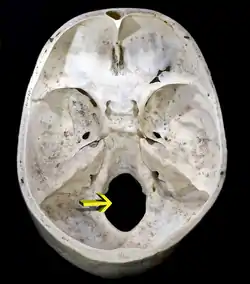

![]() Øvre overflade af kraniets nedre del. Hullet indikeret med en pil er foramen magnum. | |